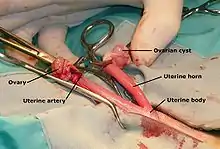

One of the most common elective surgical procedures in animals are those that render animals incapable of reproducing. Neutering in animals describes spaying or castration (also please see castration). To spay (medical term: ovariectomy or ovario-hysterectomy) is to completely remove the ovaries and often the uterus of a female animal. In a dog, this is accomplished through a ventral midline incision into the abdomen. In a cat, this is accomplished either by a ventral midline abdominal incision, or by a flank incision (more common in the UK). With an ovariectomy ligatures are placed on the blood vessels above and below the ovary and the organ is removed. With an ovariohysterectomy, the ligaments of the uterus and ovaries are broken down and the blood vessels are ligated and both organs are removed. The body wall, subcutis, and skin are sutured. To castrate (medical term: orchiectomy) is to remove the testicles of a male animal. Different techniques are used depending on the type of animal, including ligation of the spermatic cord with suture material, placing a rubber band around the cord to restrict blood flow to the testes, or crushing the cord with a specialized instrument like the Burdizzo.